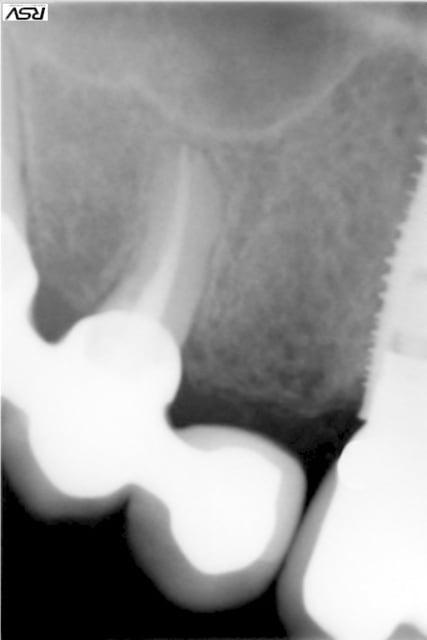

isabelleni

25/10/2013 à 00h33

voici la radio de la 21:

Si la résorption est purement interne, une obturation à la gutta est correcte. Une obturation à la BioDentine ou au MTA n'a d'intérêt que s'il y a déjà une communication endo-paro.

Les résorptions internes lorsqu'elles sont correctement obturées (ce qui à l'air d'être le cas) ont normalement un bon pronostic dans la mesure où le phénomène de résorption s'arrête.

Le seul risque est la fracture si la zone de résorption fragilise trop la dent.

Pour moi, la dent est à surveiller.

Si vous le souhaitez, je peux recevoir votre fils pour faire un Cone Beam pour contrôler.